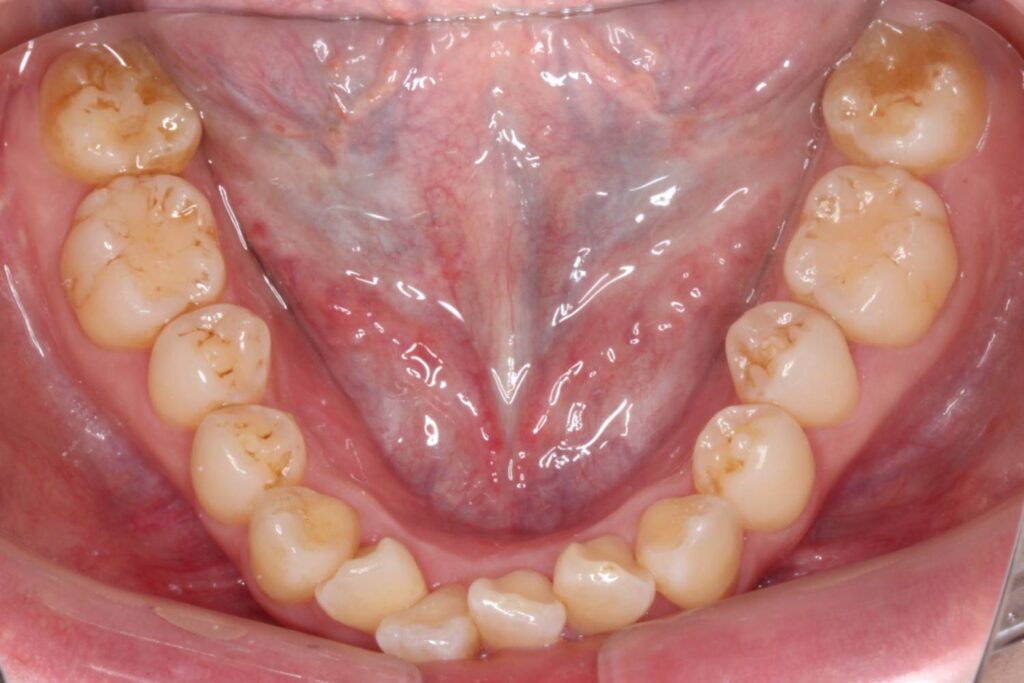

前歯に叢生があり、特に右上の前歯は前方に突出していて目立ってしまっています。

また、上顎の犬歯は「八重歯」と呼ばれる状態で、唇をよく噛んでしまったり、口内炎ができてしまうとのことでした。

奥歯の噛み合わせは、下顎に対して上顎が前方にずれてしまっています。

Before